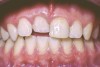

The patient's endodontic examination revealed a flexible splint from teeth Nos. 7 through 10 (Figure 1). Tooth No. 8 had a 3 mm x 3 mm class II fracture of the mesioincisal portion of the crown. Tooth No. 9 had a class IV fracture of the crown running labiopalatally from the remaining 2 mm of the crown to bone level on the palatal. A pulpotomy had been performed on the exposed pulp. Both teeth exhibited class III mobility. Teeth Nos. 7 through 10 did not respond to cold testing. None of the teeth were tender to palpation, and only tooth No. 9 had a slight positive response to percussion. Periodontal probings of tooth No. 8 were 4 mm to 5 mm on both the labial and palatal aspects. There was a narrow 12 mm probing on the straight palatal of No. 9; the remaining probing depths were 4 mm to 5 mm.2 A periapical radiograph showed both teeth Nos. 8 and 9 to have incompletely formed roots with wide-open foramina (Figure 2).

Fig 1. Age 8. Facial view of teeth Nos. 8 and 9 at initial examination.

Figure 1